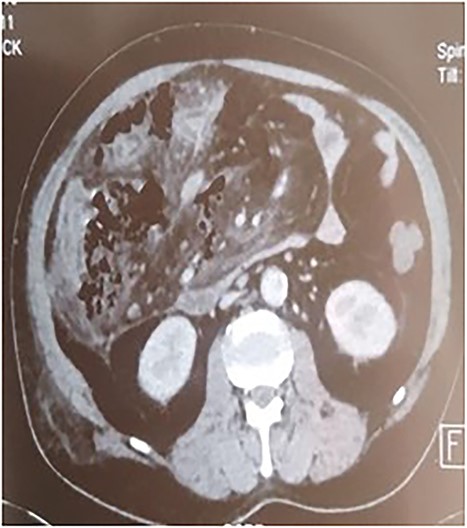

A 53-year-old man with no known medical history was admitted to the hospital because of epigastric pain persisting for 24 h, accompanied by weakness. Physical examination revealed a temperature of 39°C, severe dehydration, poor peripheral perfusion, a pulse of 110 bpm, blood pressure at 10/6 mm/Hg, a painful and tympanic abdomen without peristalsis, with tenderness over the epigastric region. Laboratory tests showed a lipase level of 667 U/l, sodium at 140 mmol/l, potassium at 4.5 mmol/l, creatinine at 106 μmol/l, urea at 6.5 mmol/l, alanine aminotransferase at 161 U/l, aspartate aminotransferase at 85 U/l, an elevated leukocyte count at 29,3 × 109/l. Abdominal CT with contrast revealed pancreatic necrosis with gas surrounding the pancreas, as well as pneumoperitoneum and in the right anterior pararenal space. Thickening of the mesentery root with lymph node enlargement (Figs 1–3).

In our case, CT plays a significant role in therapeutic management, and the presence of extra-digestive gas motivates the surgical indication [1, 3, 6].